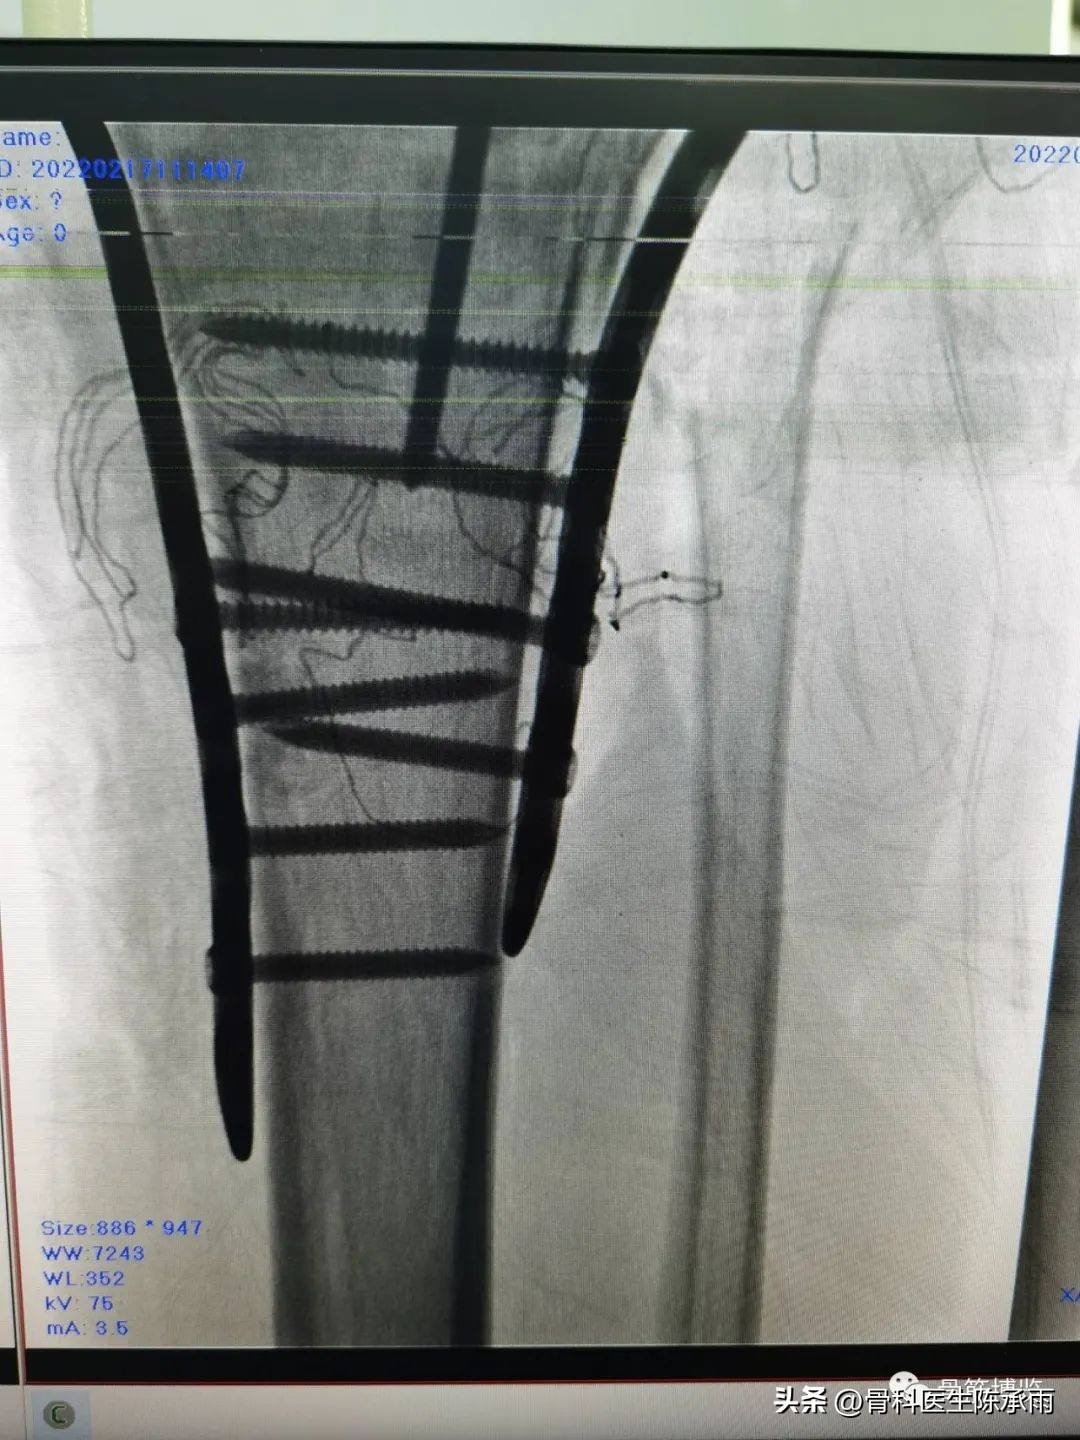

1例

2例

3例

4例

5例

6例

7例